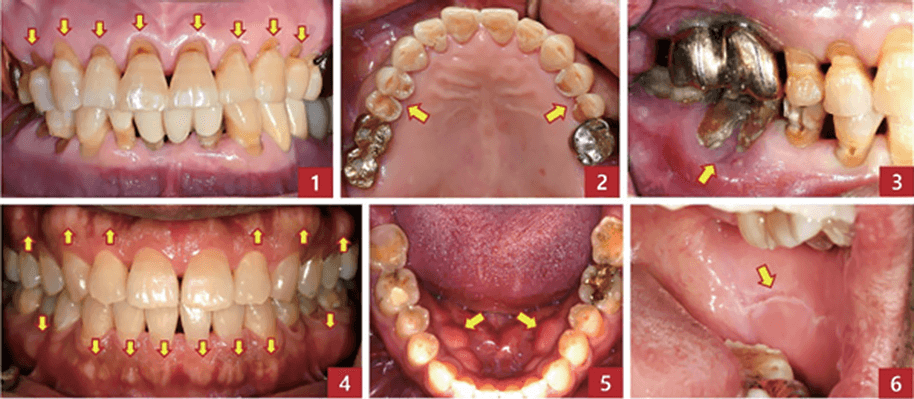

교합력이 점차 강해지고 있는 임상적 신호들. 1. 치아 목 부분이 패이는 다수의 굴곡파절(abfraction) 2. 소구치 교합면의 중등도 마모 및 파절 3. 대구치의 치은 퇴축 및 치근 노출 4. 치조골에 보이는 전반적인 골융기(exostosis) 5. 하악 설측에 나타나는 하악골융기(torus) 6. 협측 구강점막에 백색선(linea alba)으로 나타나는 치아 자국.